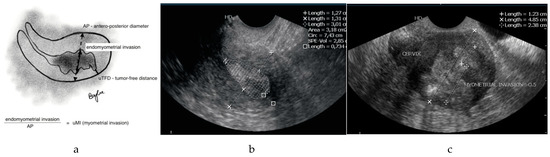

2.2. Ultrasound Examination